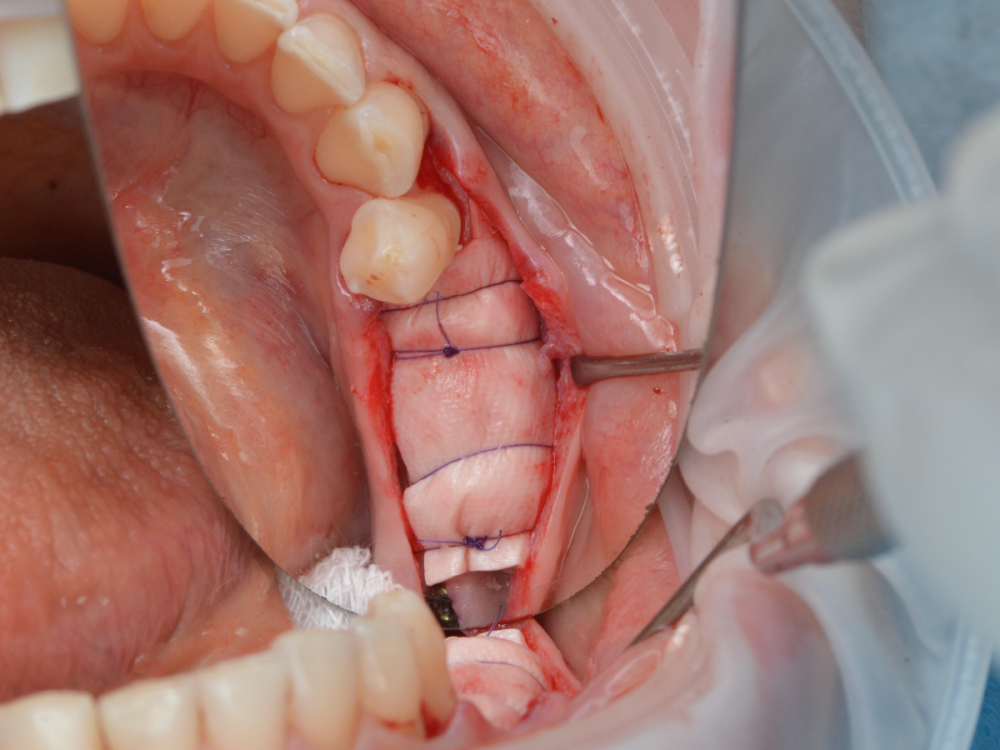

stommm Опубликовано 27 октября, 2023 Поделиться Опубликовано 27 октября, 2023 (изменено) Всем доброго времени суток. Описание на слайдах Изменено 27 октября, 2023 пользователем stommm 13 1 Ссылка на комментарий

stommm Опубликовано 27 октября, 2023 Автор Поделиться Опубликовано 27 октября, 2023 Вот из книги Урбана фото. Честно говоря не помню что в 2014 говорил Олег Пономарев, думаю если заглянет в эту тему, прокомментирует сам. Что по этому поводу говорит Джованович (пару раз слушал его на конгрессах разных) тоже не знаю) остальных не уверен что слышал вживую или читал их мнение, так что тоже хз) Ссылка на комментарий